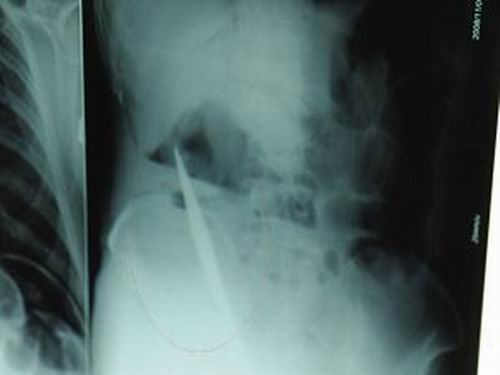

X光片上,尖刀清晰可見。

從男子體內取出的尖刀足足有19厘米長。

昨天(11月6日)上午,記者在徐州礦務集團總醫(yī)院重癥監(jiān)護室見到了這名男子,目前他雖然已經恢復了意識,但還不能開口說話,需要呼吸機輔助呼吸。據醫(yī)生介紹,4日中午12時左右,這名男子因服毒輕生被緊急送到醫(yī)院進行搶救,之前,這名男子已經在當地鄉(xiāng)鎮(zhèn)醫(yī)院進行了近20小時的治療,但效果不佳!安∪吮晦D院到礦總院時已神志不清,血壓極低,處于休克狀態(tài)。”救護人員給男子洗胃、初步處理以后,發(fā)現(xiàn)男子呼吸急促,于是趕緊給他拍片檢查。結果讓所有的醫(yī)生大吃一驚,竟有一把尖狀異物橫在該男子腹腔內!當天下午5時30分,輕生男子被推上了手術臺。經過40多分鐘的手術,該男子腹腔被打開,手術醫(yī)生發(fā)現(xiàn),男子體內的金屬狀異物竟然是一把長19厘米的尖刀!